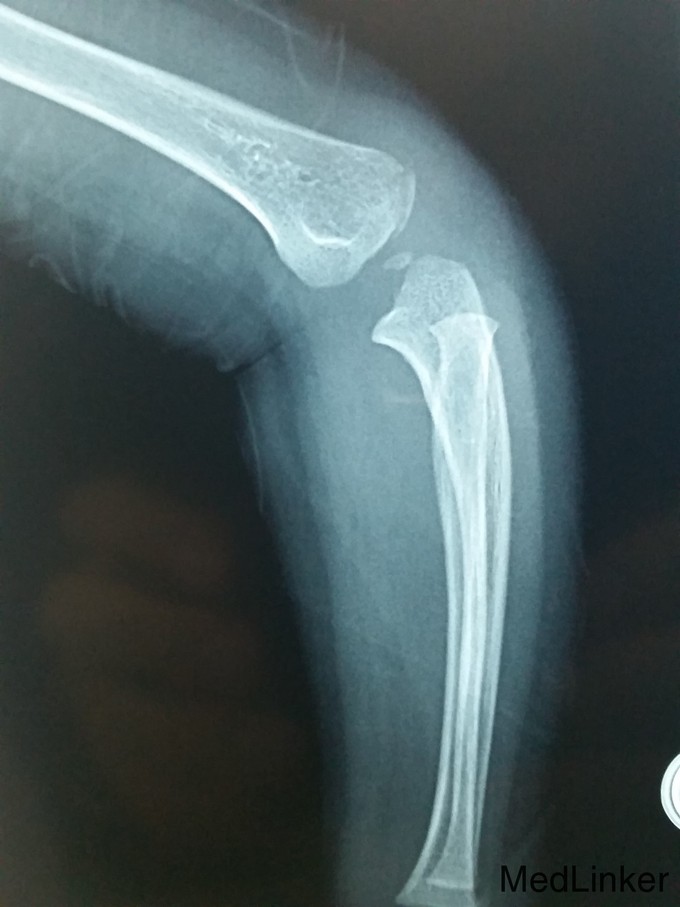

复杂骨折

骨折

男,1岁10月,约1米高台跳下时伤及左侧肘部,肿胀活动受限

左上肢石膏长臂石膏后托固定,左手活动可

请教各位诊断及治疗方案